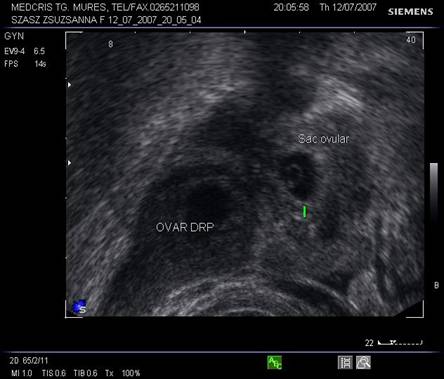

Fig nr 59 Aceeasi sarcina ca in figura precedenta, in sacul ovular marcat cu o linie, se distinge clar sacul lui Yolk, alaturi de corpul galben ovarian drept

Fig nr 60 Sarcina extrauterina tubara (ampulara , dg intraoperator) cu embrion evident de cca 6 sapt( intre calipere)